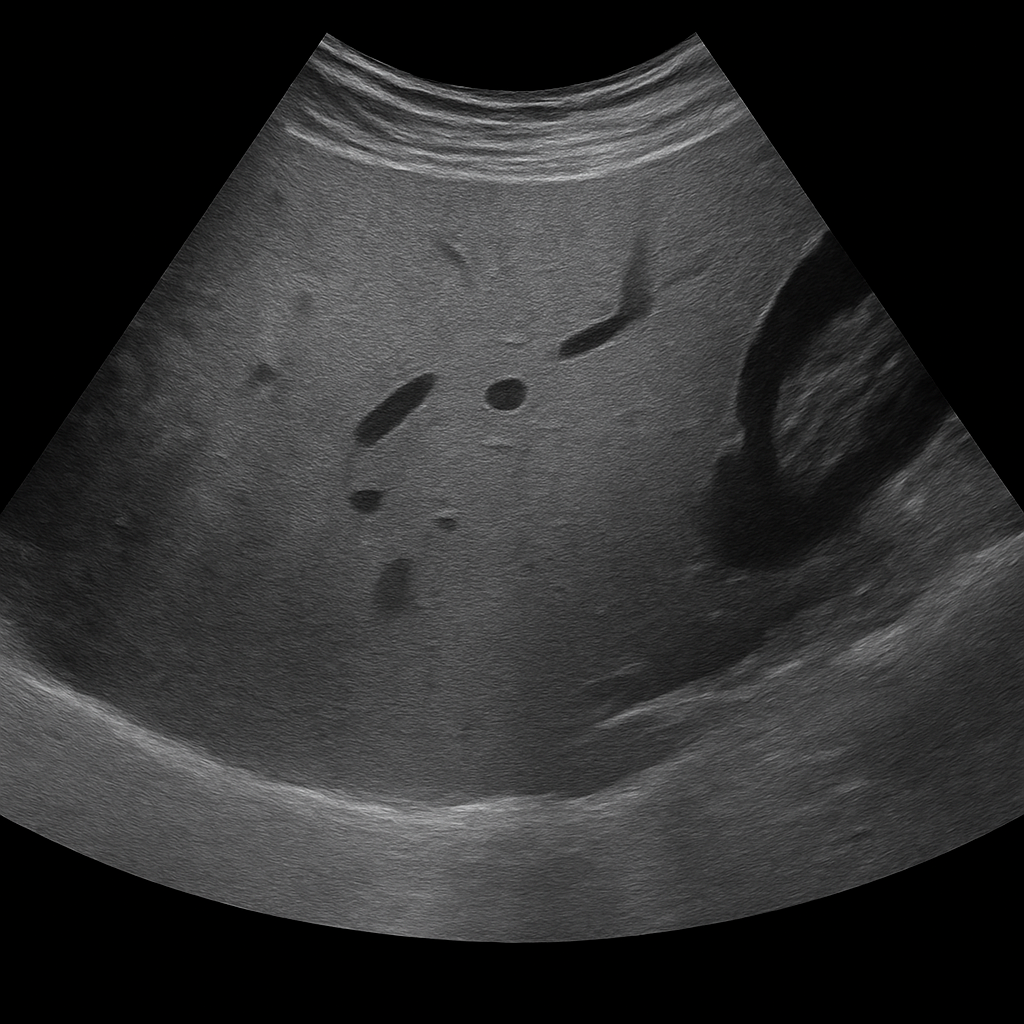

MRI Abdomen/MRCP

MRI of the abdomen

- Abdominal MRI visualizes the liver, kidneys, bile ducts, and pancreas.

- Recommended for abdominal pain or suspected abnormalities.

- MRCP shows bile and pancreatic ducts – without contrast agents.

- Radiation-free exam with referral and specialist report included.